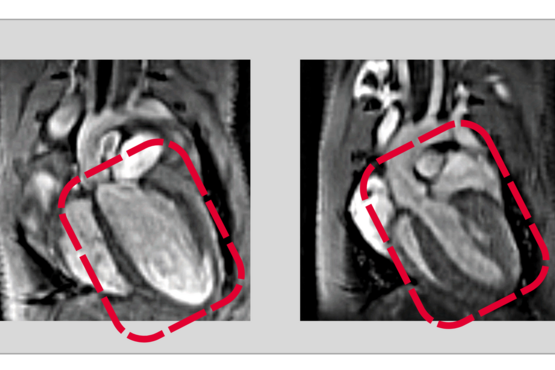

Komplexe Steuerungsprozesse für ein komplexes Organ: Wie zwei verwandte Proteine zusammenarbeiten um die Entwicklung des Herzens zu steuern.

RBPMS und RBPMS2 regulieren Zellteilung und -funktion während der Herzentwicklung